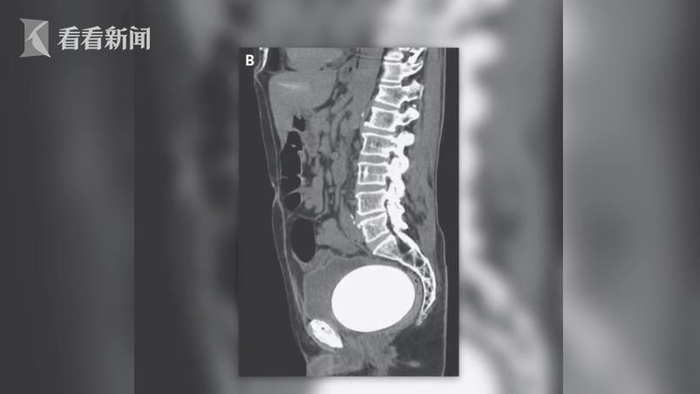

美国加州一名64岁男子因腹部疼痛、排尿困难就医,医生通过电脑断层扫描发现,患者下体竟然长了好大一颗“蛋”,原来是巨大的膀胱结石,尺寸为12x9.5cm,重达770克(约1.5斤),由于体积实在过大最后只好动手术取出,看起来与一颗鸵鸟蛋差不多大。

这起特殊案例刊载在《新英格兰医学杂志》中,医生通过断层扫描,除了在腹部发现巨大膀胱石,在左边输尿管也发现另一颗小结石,最后以激光方式震碎。医生表示:“男子10年前曾患膀胱癌,被当时的主治医生切除了膀胱,现在使用的是重建的人工膀胱,虽然能连结输尿管和尿道,让尿液顺利排出,但会增加结石的风险。”